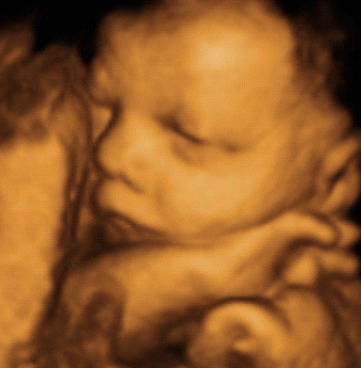

3D/4D scan are not usually need for medical reasons. Some people refer to them as "entertainment scans". If you are having a 3D/4D scan, we always do a wellbeing scan first before trying to view the face or other body parts. It may take some time to get a good view of the baby. If the baby is not in a favourable position, you may be asked to take a break and move around to see if the baby will also move.